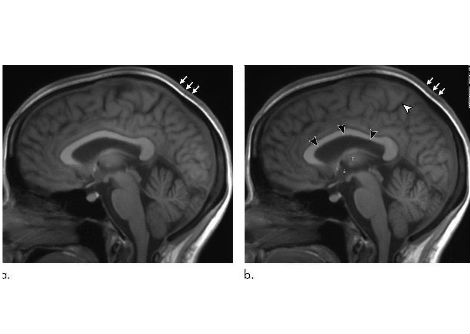

في عدد أبريل 2021 الصادر عن The Scientist ، يفترض العالم / المؤلف Paul Mischel من جامعة ستانفورد وجود توازن مثير للاهتمام بين التقدم العلمي في مجال علم الفلك وكيف يستكشف علماء الأحياء العالم الحي. يشرح ميشيل في قصته المميزة ، "السرطان قد يكون مدفوعًا بالحمض النووي خارج الكروموسومات" ، كيف يمكن للخرائط في كلا المجالين أن تقود اكتشاف الحقائق العلمية وتوصيفها عن مسارها أحيانًا. في حالة علم الفلك ، تضمنت الخرائط عرض بطليموس المتمحور حول الأرض للكون والخرائط المصححة التي تم إجراؤها بعد 1400 عام بواسطة القديس الراعي لعلم الفلك ، المفكر في عصر النهضة نيكولاس كوبرنيكوس. في حالة السرطان ، تفقد خرائط الجينوم عنصرًا رئيسيًا: الحمض النووي خارج الصبغيات (ecDNA). يشبّه ميشيل القفزة المفاهيمية المتمثلة في اعتماد نموذج محوره الشمس للنظام الشمسي بما هو مطلوب الآن في مفهوم العلم لديناميكيات السرطان.

وهذا هو الوعد الذي تحمله الرؤى مثل دور ecDNA. قد يؤدي دمج هذا المكون الجديد في النماذج الحالية لديناميكيات السرطان إلى طرق جديدة للتغلب على المرض ، في العديد من تعابيره المميتة. إن دمج ecDNA في الخرائط الجينية القديمة للسرطان ، والتي تركز على الحمض النووي الصبغي الأكثر قابلية للتتبع ، لا يقلب النموذج بأكمله. إنه فقط يعيد تركيزه بطريقة قد تؤدي فقط إلى تحويل مركز الثقل للعاملين الجزيئيين المخططين بدقة. مثل تلسكوب جاليليو ، تؤكد التقنيات الجينومية المتقدمة التأثير البيولوجي للـ ecDNA وتسمح للباحثين بالعثور على المزيد والمزيد من السياقات التي قد تؤدي فيها المكونات الجينية التي تم تقديرها حديثًا إلى حدوث المرض.